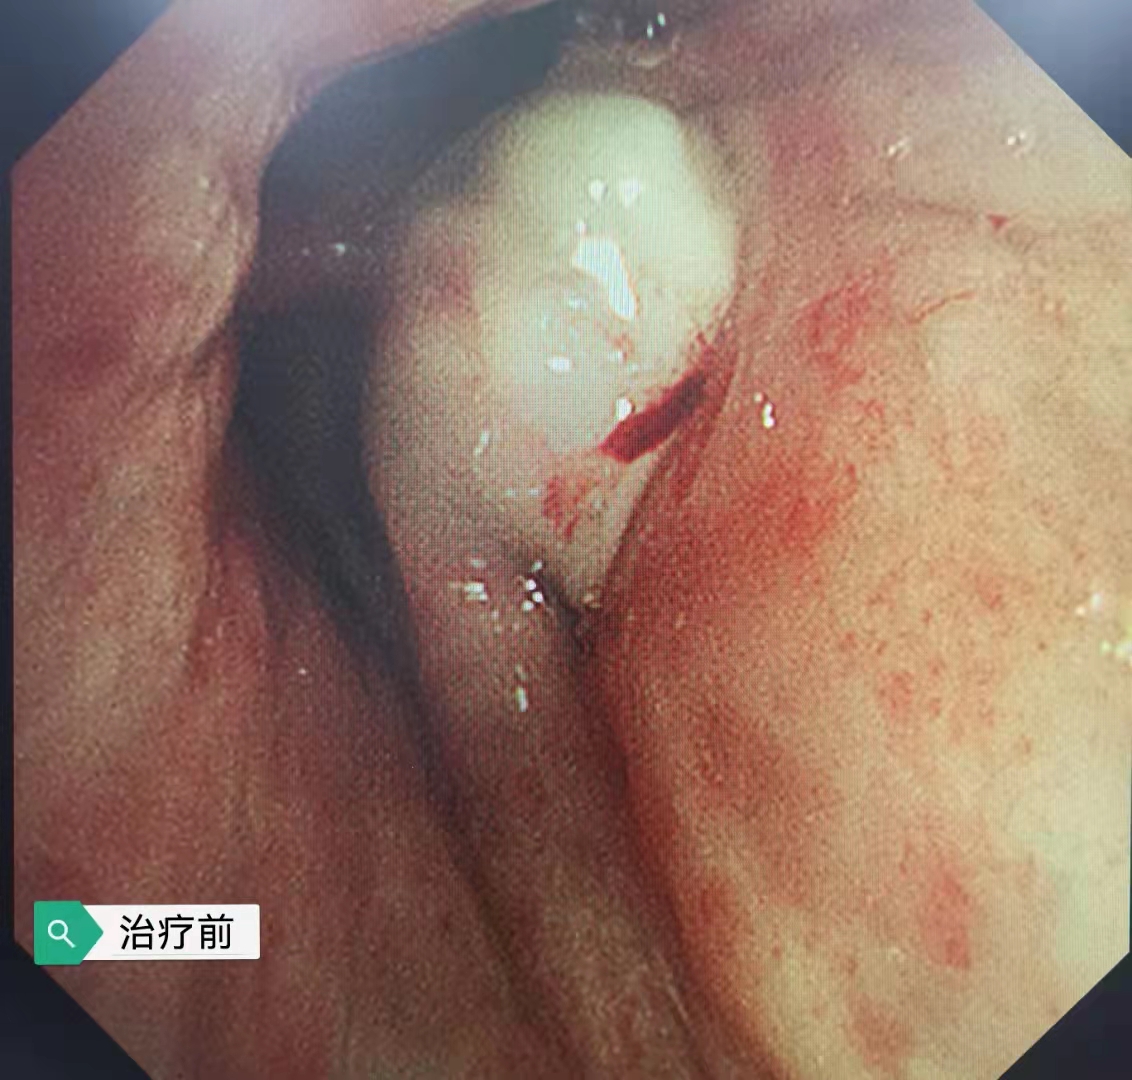

今日再次為一例肺部占位合并氣道內(nèi)腫瘤的患者施行支氣管鏡下的介入手術(shù),術(shù)前呼吸困難、心律失常二聯(lián)律,術(shù)后患者呼吸困難明顯緩解,且心律失常得以糾正,效果立竿見影。但是影像學(xué)的巨大腫塊,還需要結(jié)合病理分型采取恰當(dāng)?shù)木C合治療手段來減緩和控制疾病進(jìn)展。呼吸介入,我們團(tuán)隊一直在前進(jìn)中。